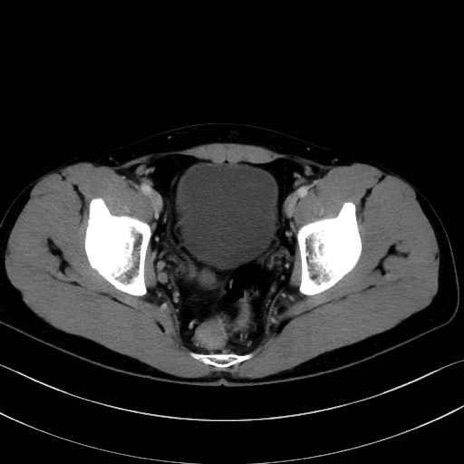

内閉鎖筋 (Obturator internus)

外閉鎖筋 (Obturator externus)

大腿方形筋 (Quadratus femoris)